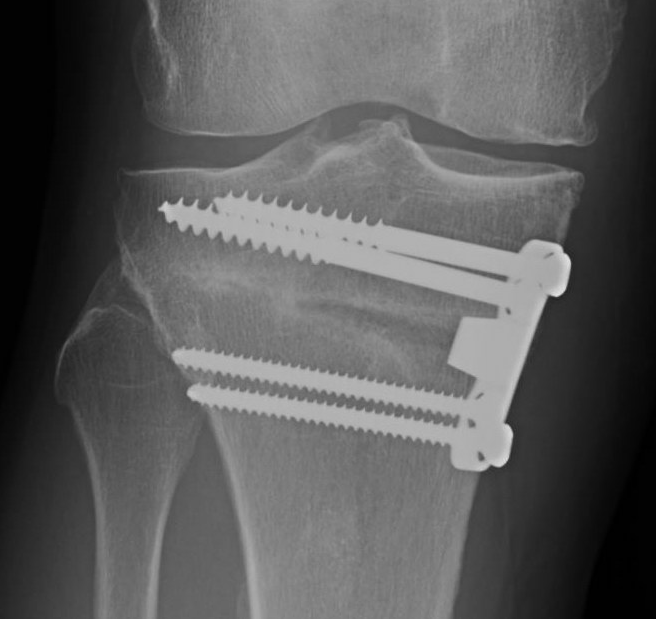

Stabilisation

- locking plates

- +/- autograft / allograft / synthetic bone graft

Arthrex Locking Puddhu plate PDF

Arthrex ContourLock system PDF